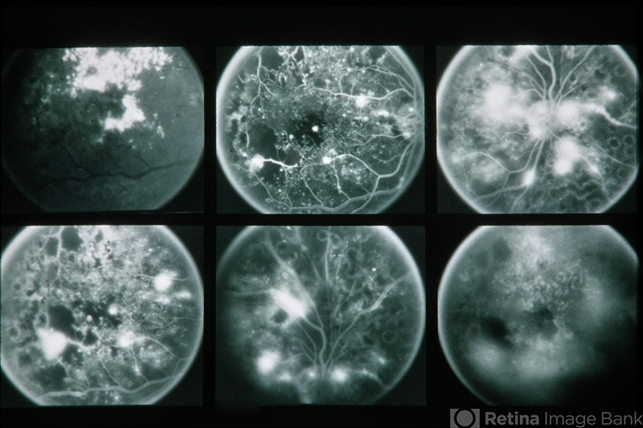

- 67-year-old black female. Re 20/200 LE 6/200. Proliferative diabetic retinopathy (laser error).